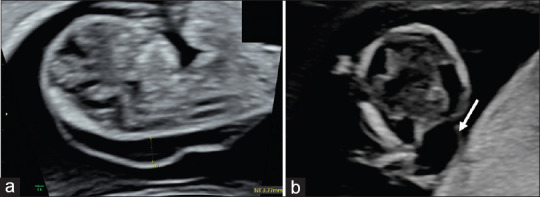

A Pattern of Malformations in the First Trimester Ultrasound.